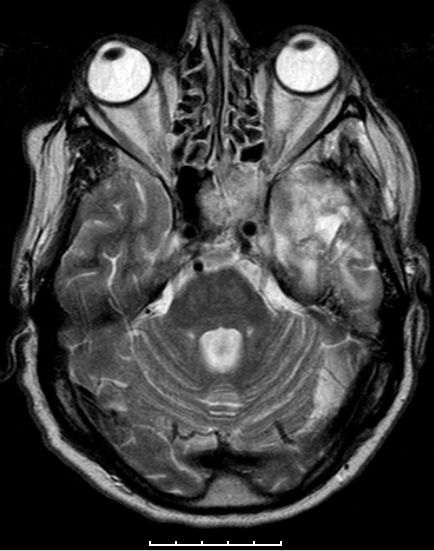

Glioblastome metastasieren normalerweise nicht außerhalb des ZNS. | |

| Fall | Im vorliegenden Fall kam es während der Temodal-Therapie nach postoperativer Radiochemotherapie zu einen Durchbruch des GBs durch die Schädelbasis. | |